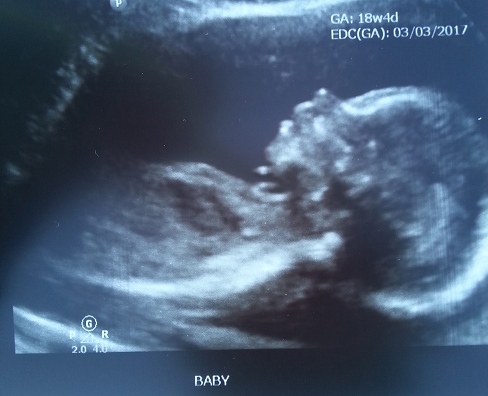

Had my anatomy scan last week at 18 weeks. We are expecting a healthy little boy!

Me: 27 - DH: 33

Married: June 2011

TTC #1: January 2016

BFP #1: February 22nd 2016 MC w/ Misoprostol: March 21st 2016 -Blighted Ovum

BFP #2: July 6th 2016 EDD: March 15th 2017